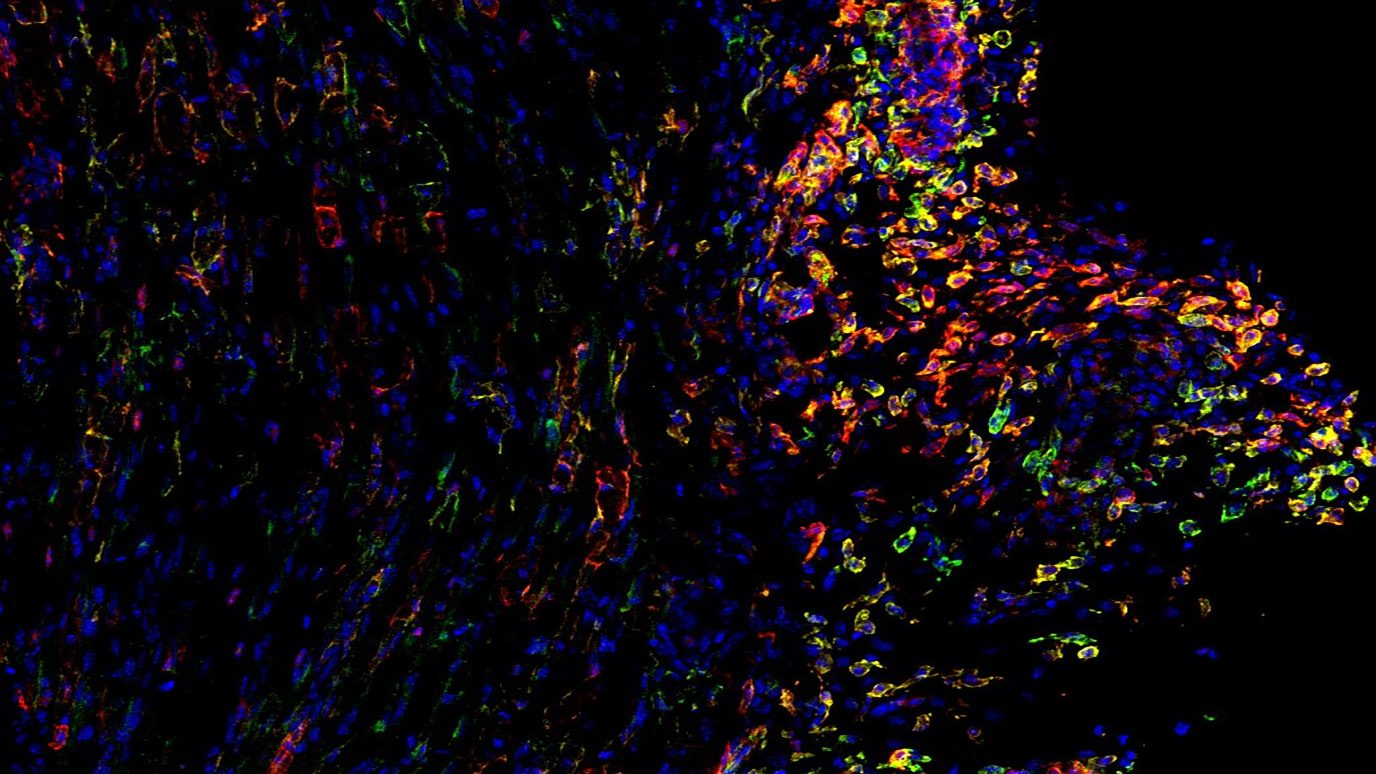

Landmark study maps spatial organization of cancer-associated fibroblasts across cancers

Cancer-associated fibroblasts (CAFs) are essential...